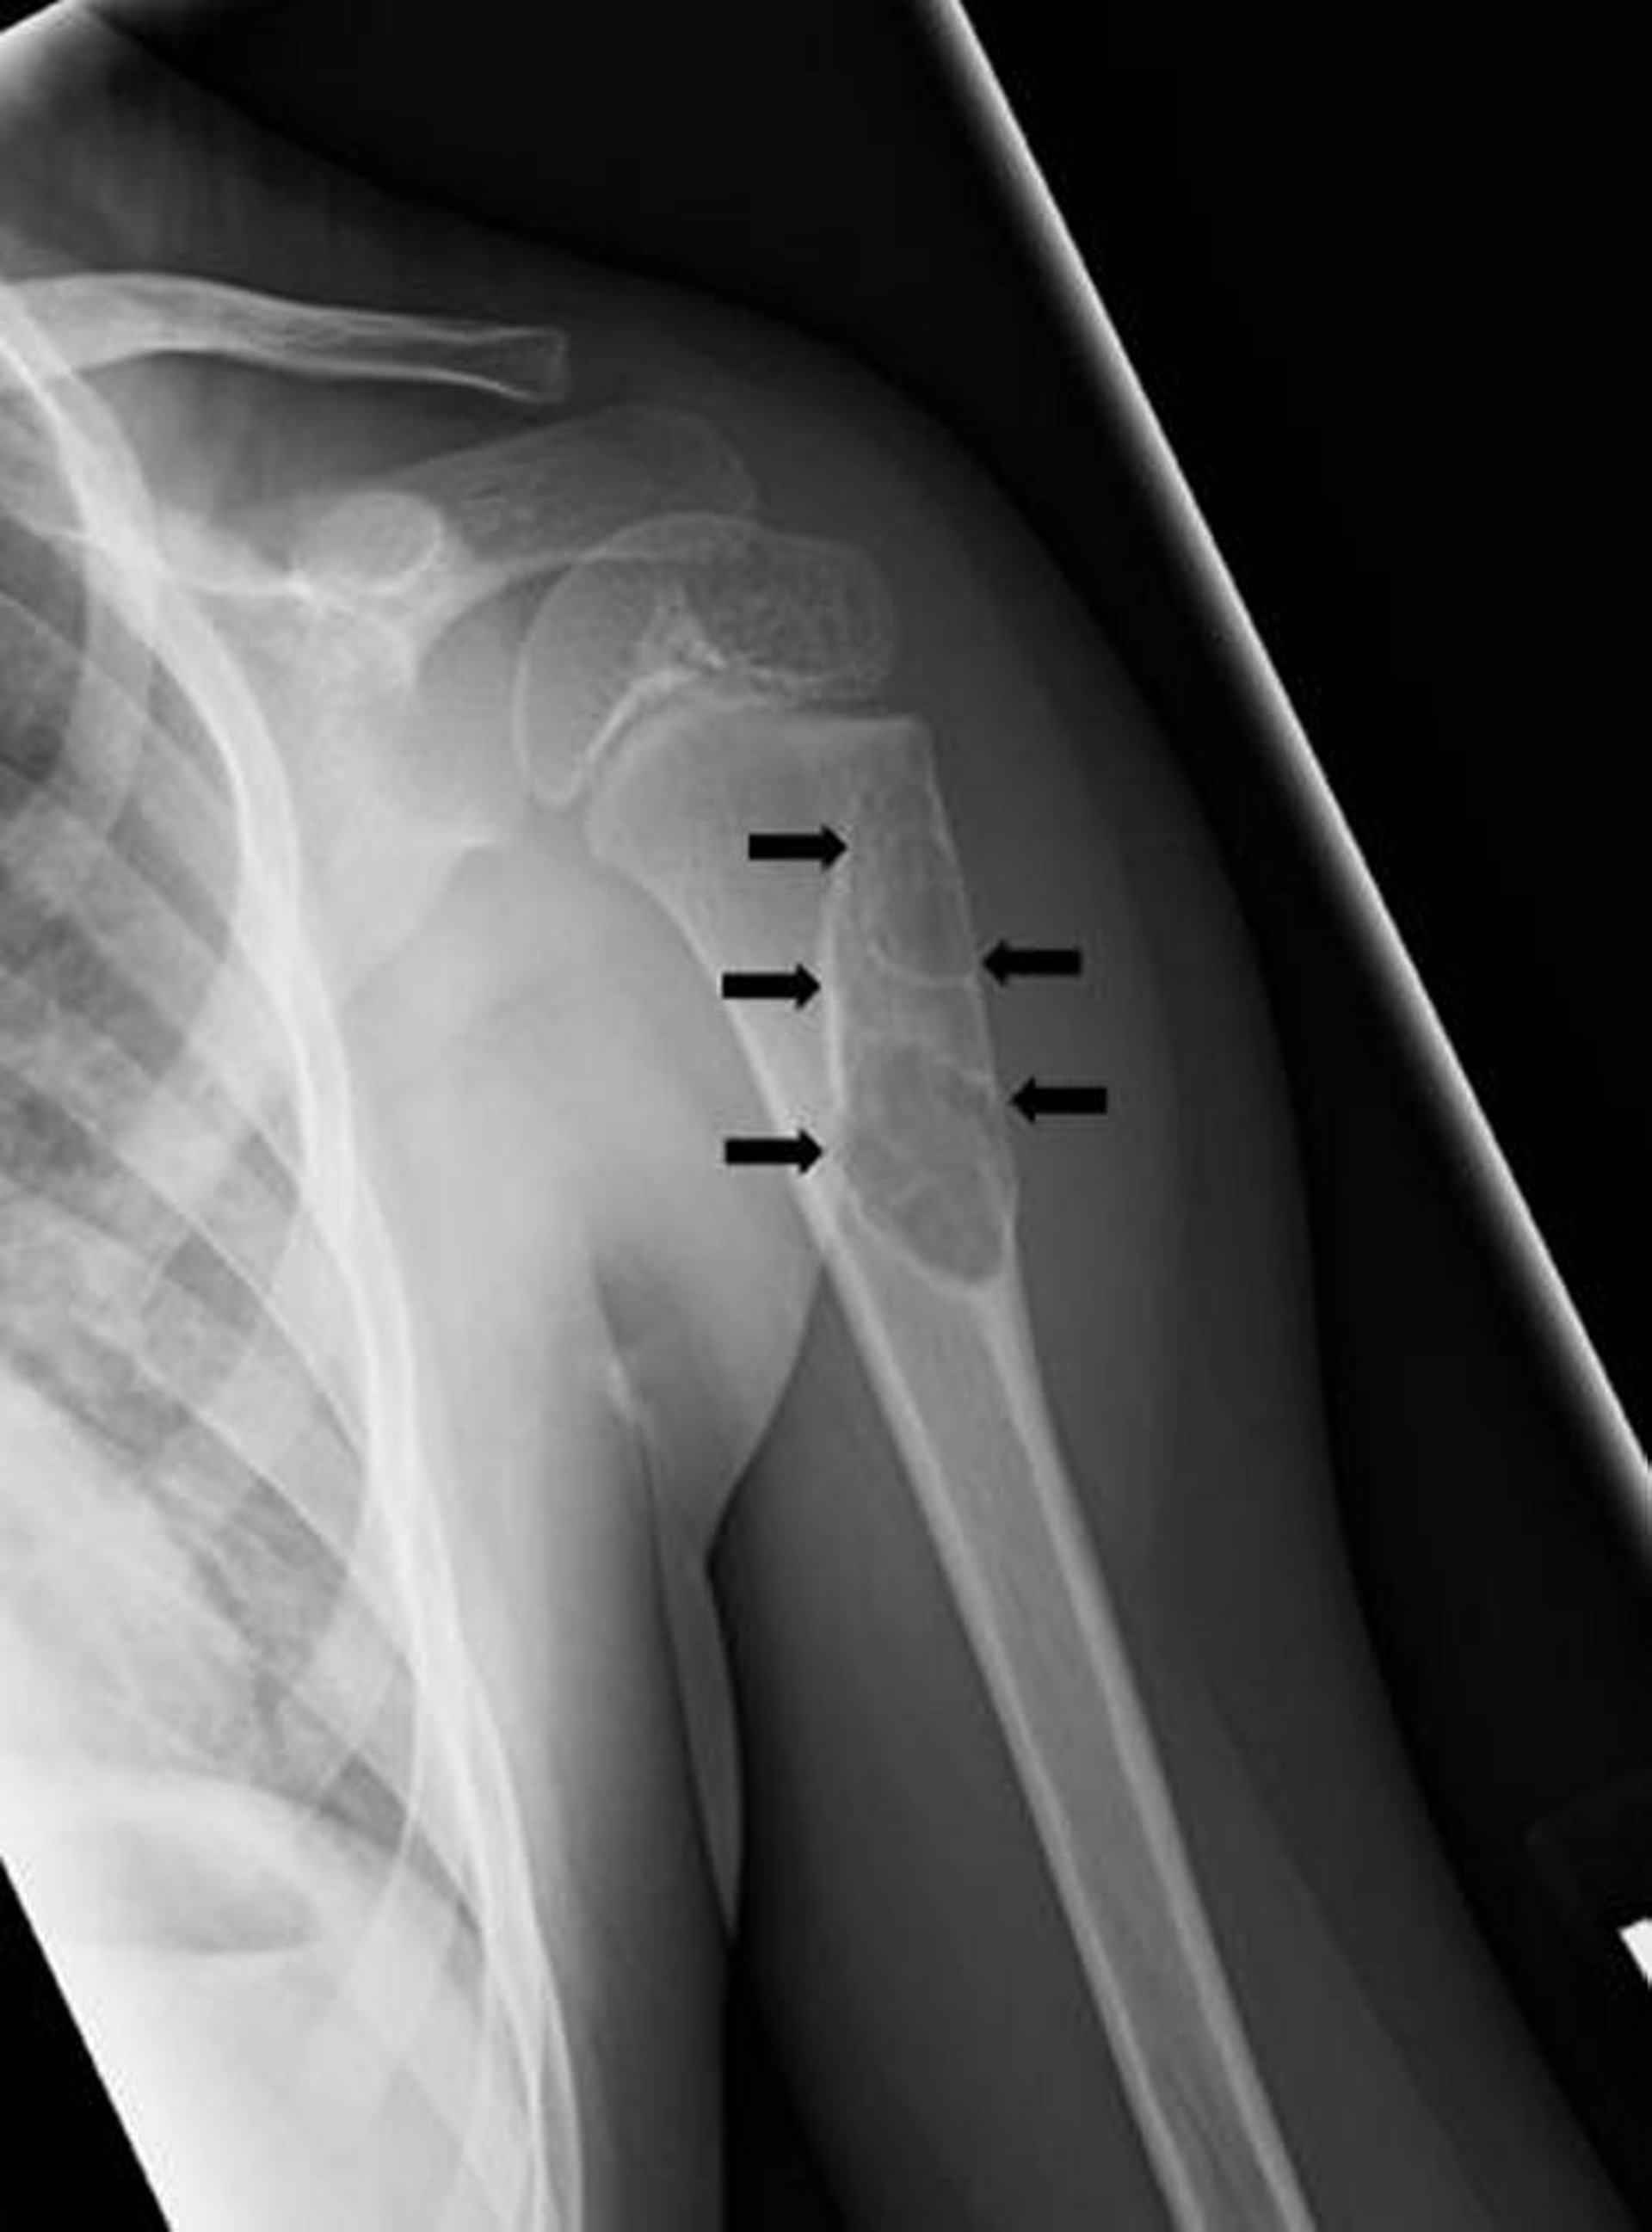

Cette radiographie montre un kyste osseux solitaire simple (flèches) au niveau de l’os de l’avant-bras.

Image publiée avec l’aimable autorisation des Drs Michael J. Joyce et Hakan Ilaslan.